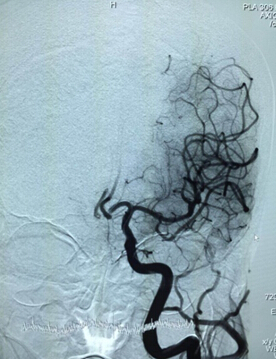

取栓重建手术进行中 左侧颈内动脉血管已通

人体脑内的结构纷繁复杂,老人左侧颈动脉又过度迂曲、转角过大,结构纷繁复杂如同迷宫,为了穿过这个迷宫,找到血栓,他们用柔软材料制成的导管经由股动脉送到了指定位置,一根细细的取栓装置被缓缓送入导管内,到达血栓处的取栓装置展开了网状的前端,撑开了闭塞的血管并与血栓结合在一起,5分钟后,随着取栓装置的回撤,神经内科团队看到了装置前端取出的暗红色小血块——这就是造成脑卒中的“罪魁祸首”,即刻造影提示左侧大脑血管开始逐渐清晰显现,血流正在流动并充盈着左侧大脑血管。

就在大家刚刚松了一口气的时候,脱落后的血栓竟然随着血流堵住了左侧另一只大血管——左侧大脑前动脉,造影显示,左侧另一只大血管的“树枝”慢慢消失了。现场指挥蔡艺灵当机立断,迅速开展第二次取栓,当神经血管重建装置在左侧大脑前动脉血管内释放展开时,即刻造影提示左侧大脑前动脉血流部分再度通畅,这一次,装置前段牢牢抓住了“逃跑”的血栓,将取栓装置撤出体外后,取出了大块的暗红色血栓。